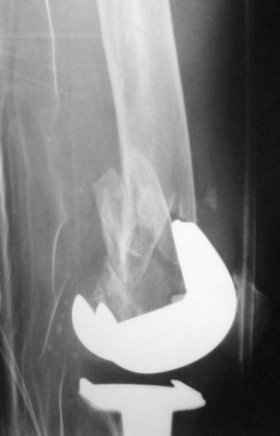

Peri-prosthetic femoral fracture

78 year old lady.

IB 2 knee replacement in 1999.

Well functioning implant. Fell at home last week on the stairs and has this fracture.

The rest of the femur and tibia are intact. Slim build. Good medical condition. Problems: 1). There is very little bone distal to the fracture.

2). There is rather limited room between the condyles in an IB2 knee for a retrograde nail.